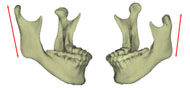

3차원 입체영상의 활용은 여러 가지 방향으로 가능한 반면 저자의 경우에는 안면비대칭 환자에서 “어느 구조물의 좌우 차이가 이부편위(chin deviation)를 야기하였는가”의 파악에 3차원 입체영상이 필요하였으며 이의 사용결과 2차원사진으로는 알 수 없었던 여러 가지를 이해할 수 있게 되었다. 얼핏 생각하면 이부편위는 좌우 ramus의 길이 차이 때문에 나타난다고 이해할 수 있다. 그러나 ramus 길이 뿐 아니라 mandibular body 길이차이에 의해서도 이부편위는 나타날 수 있고 이러한 부위별 파악은 특히 수술계획 수립에 매우 중요하다. 또한 어떤 환자에서는 ramus의 길이나 body의 길이는 좌우가 비슷한데, 정면에서 보았을 때 또는 측면에서 보았을 때 ramus의 경사도 차이로 인해 이부편위가 나타난 것을 발견할 수 있었다. 이러한 ramus 경사도 차이는 측모두부방사선사진이나 정모두부방사선사진에서도 관찰될 수 있지만 2차원적 사진의 경우 projection error로 인해 평가에 확신을 할 수 없는 반면 3차원 입체영상의 경우에는 이미지를자유자재로 돌려볼 수 있으므로 보다 용이하게 그리고 정확하게 이해를 할수 있었다. 3차원 입체영상을 통하여 외관상 보이는 이부편위의 원인을 살펴본 결과 저자는 (1)상악고경의 좌우차이 (2)ramus 길이의 좌우차이 (3)전방에서 보았을 때 좌우 ramus inclination의 차이 (4)측방에서 보았을 때 좌우 ramus inclination의 차이 (5)mandibular body 길이의  좌우차이 (6)mandibular body 윤곽의 좌우차이 등 6가지가 이부편위에 기여함을 발견할 수 있었다 (그림5).

그림 5. 이부편위에 기여하는 요인들. 이부편위는 단순히 ramus의 좌우차이에 의해서만 나타나는 것은 아니다. 3차원이미지를 자세히 관찰해 보면 상기 6가지 부위에서의 좌우차이가 환자로 하여금 "턱이 돌아갔다"고 느끼게 하고 있음을 알 수 있다. a. maxillary height; b. ramus length; c. frontal ramal inclination; d. lateral ramal inclination; e. body length; f. body height.